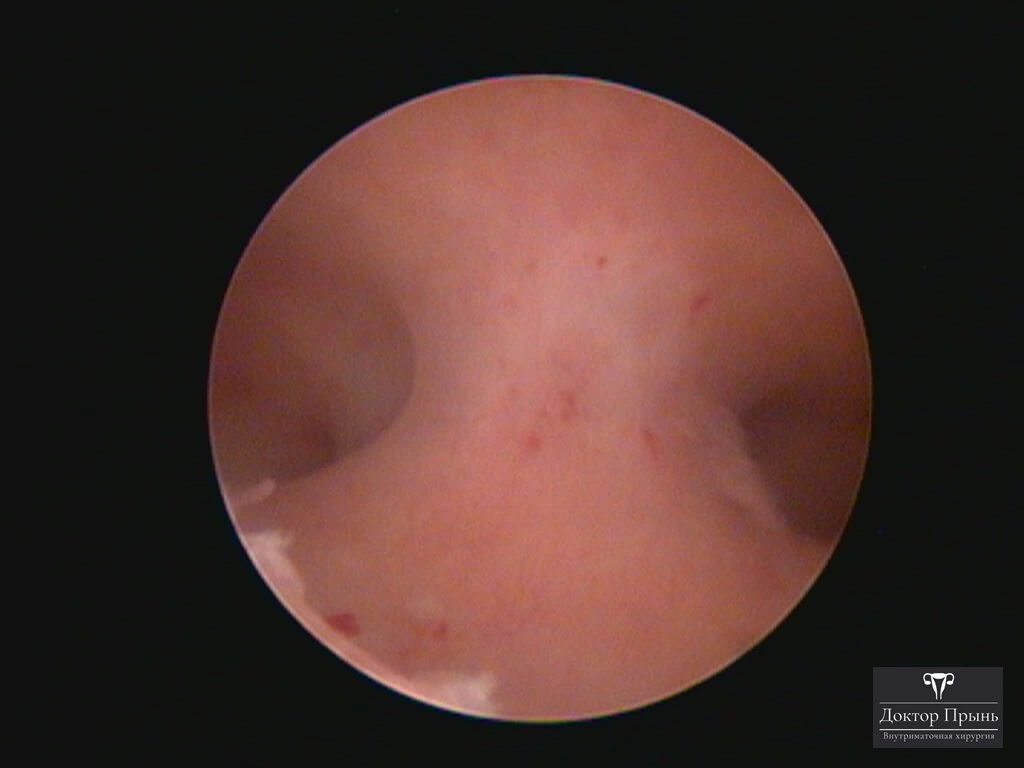

Как правило, синехии находят при УЗИ. Когда по УЗИ патологии нет, а симптомы есть, выполняют гистероскопию – это золотой стандарт в определении синехий.

Гистероскопия позволяет не только увидеть спайки, но и сразу вылечить, т.е. рассечь их. Большинству пациенток подойдёт офисная гистероскопия без наркоза и госпитализации. Среднее время операции 15 минут. Иногда требуется 2-4 операции, чтобы восстановить полость матки.

Крайне важен способ разделения спаек. Если это холодный инструмент, например, ножницы, то вероятность рецидива низкая. Плюс не повреждается нормальный эндометрий. Если рассекают горячей электропетлёй, то, наоборот, риск рецидива высокий и можно обжечь эндометрий.

Синехии, рассечённые Прынь Д.В.